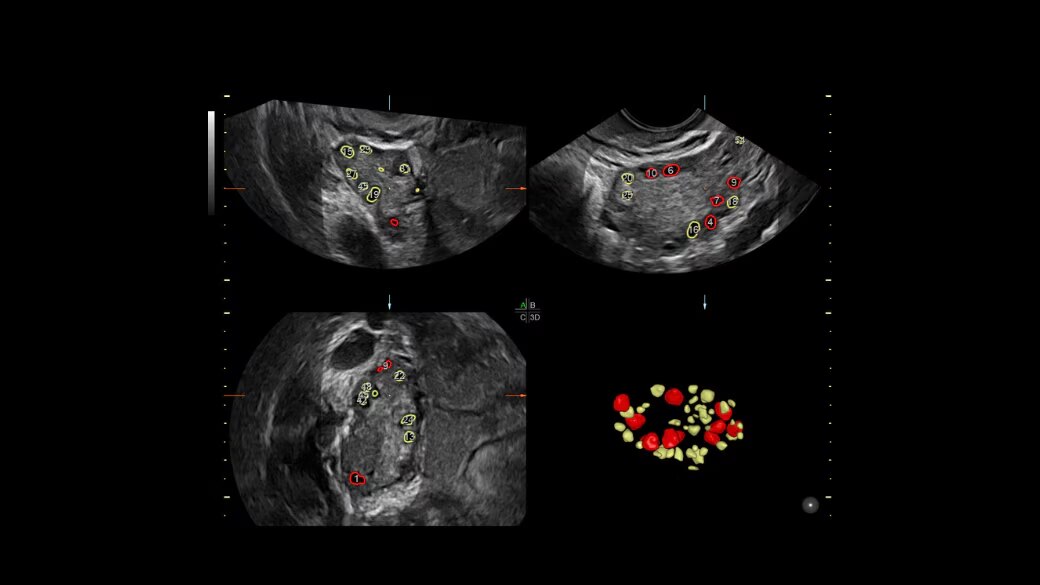

SonoAVC™ antral

Automate ovarian reserve assessment in 3D.

• Automatically counts antral follicles